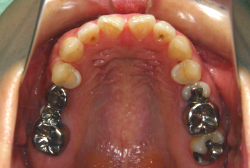

「左奥歯でものが噛めない」という主訴で来院したケースです。診断の結果、基本的には「叢生」という隙間が足りないと言うことが原因の凸凹症例でしたが、左下の乳歯が高校生になってもまだ残存している状態で、そのせいで噛み合わせが極端に悪くなっていました。

検査の結果、乳歯の下には後継ぎの永久歯が先天的に欠如していました。配列の凸凹が厳しく非抜歯で矯正することは難しく、仮に無理をして非抜歯治療をしても後々「後戻り」が懸念されることから、このような症例の場合は通常、上下顎左右第一小臼歯を抜歯させていただくのですが、左下は乳歯を抜歯して、第一小臼歯は残すことにしました。これで結果として、小臼歯部を上下左右で一つずつ減らしたのと同じ状況になります。治療後は歯並びが綺麗になっただけでなく、噛み合わせ的にも正しい状態が確立しています。

このように、先天的に永久歯が足りないという症例は最近増えています。親知らずはなくても特に問題になりませんが、その他の歯が足りないと言うのは審美的にも機能的にも重大な障害となります。しかし、矯正治療を正しく行えば、結果として歯がすべてあった場合と全く同じ仕上げにすることも可能です。